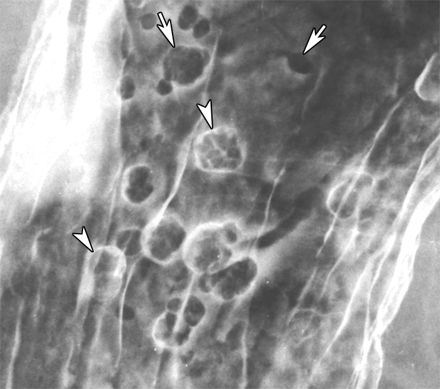

“Bull’s Eye” / Target lesion DDx